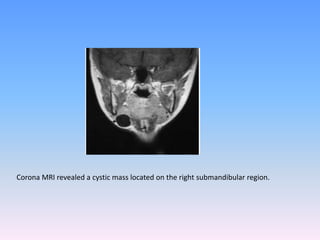

CT and MRI are the main facilities of diagnostic imaging.

Corona MRI revealed a cystic mass located on the right submandibular region.